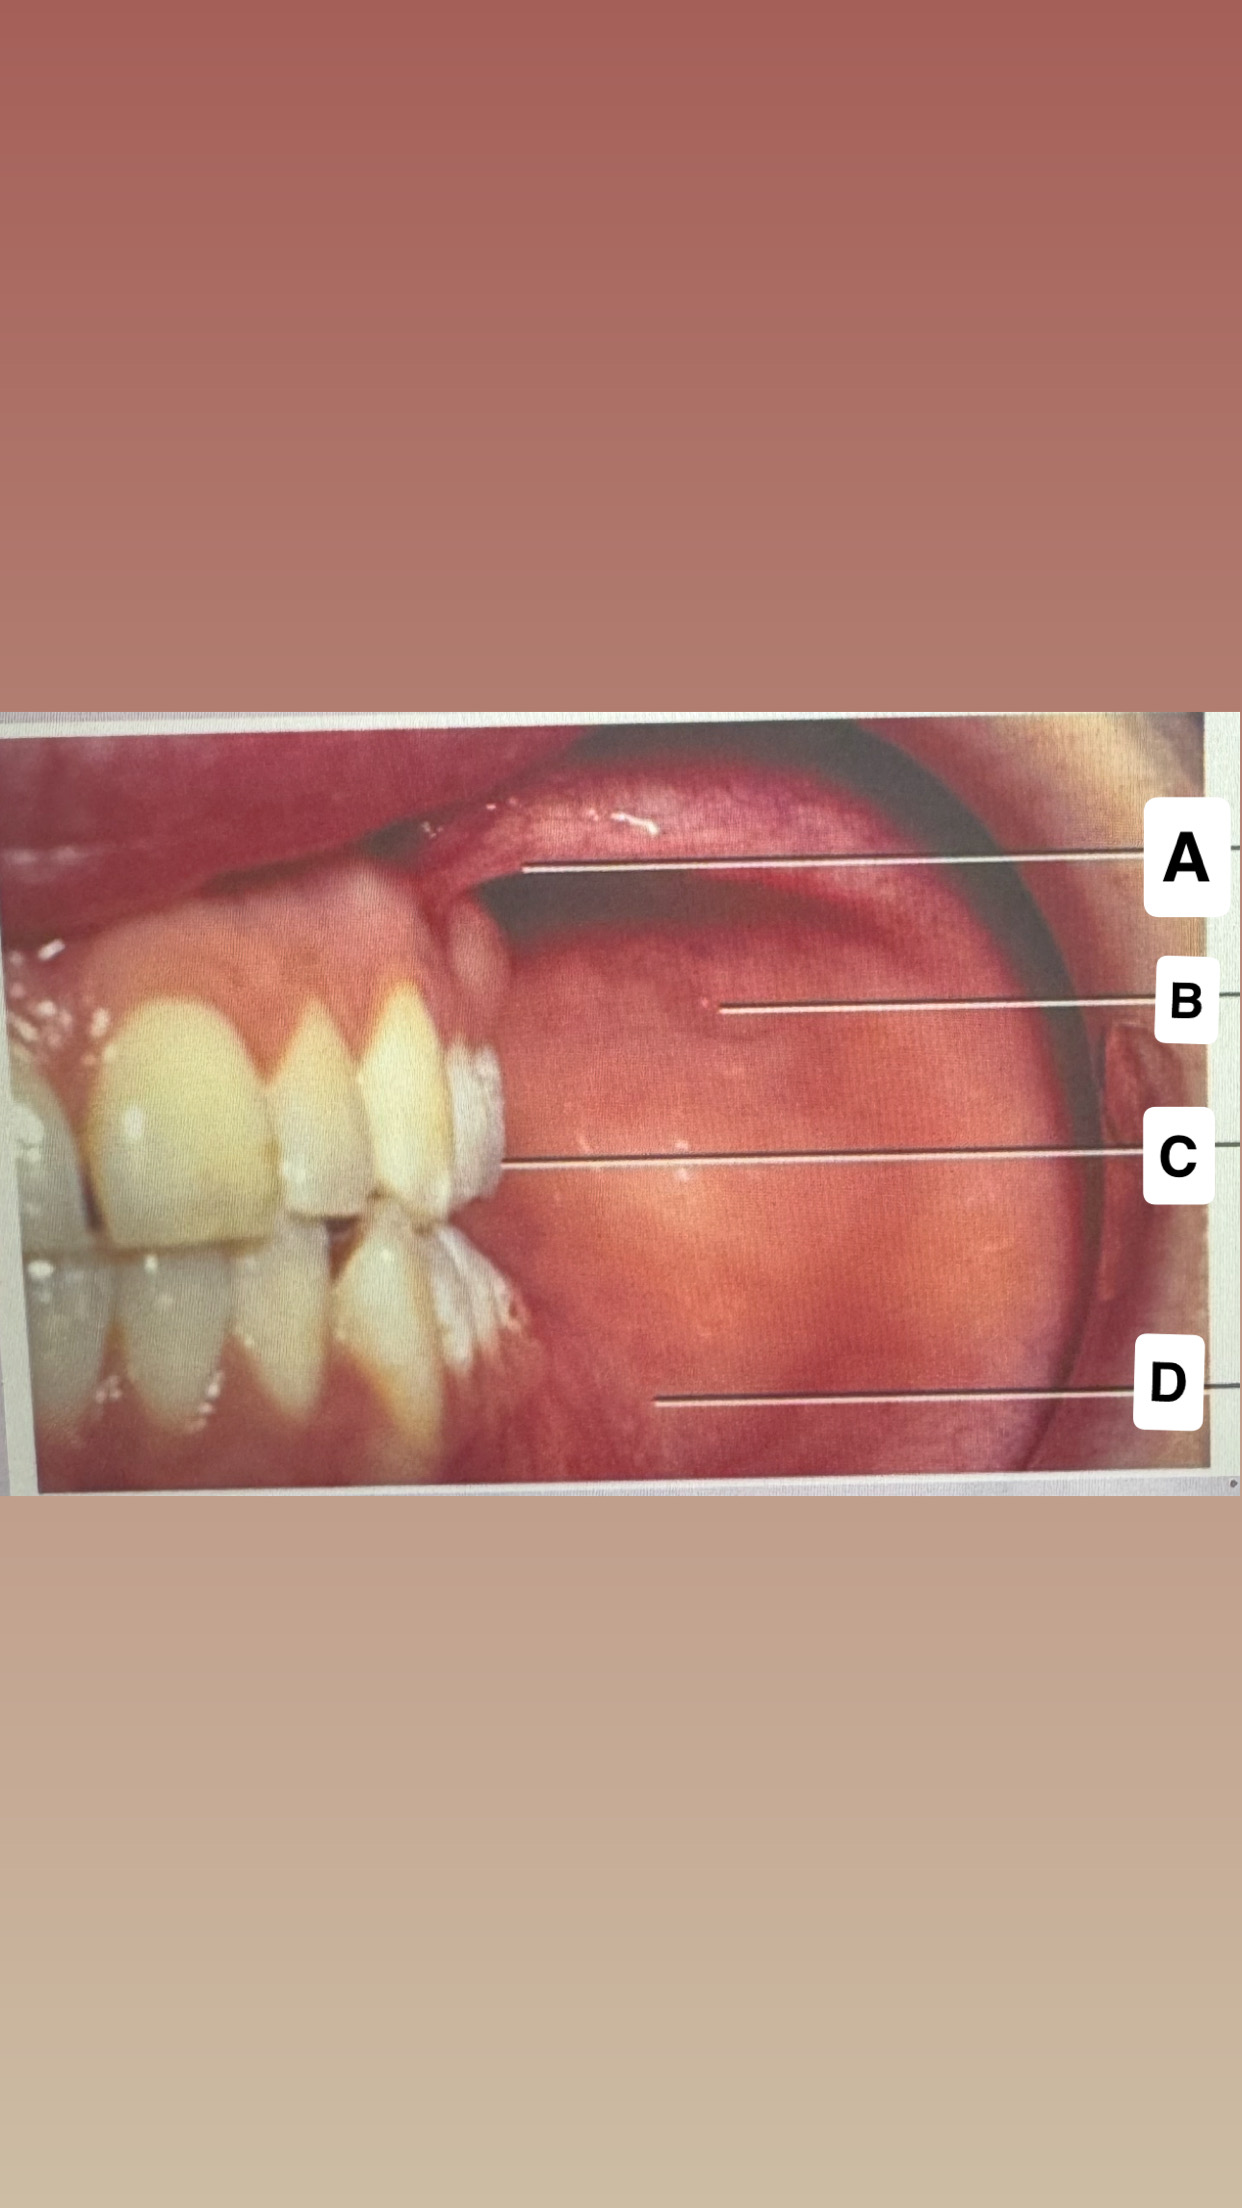

<p>Identify 1</p>

attached gingiva

<p>Identify 2</p>

gingival margin

<p>Identify 3</p>

interdental papilla

<p>Identify 4</p>

mucogingival

junction

<p>Identify 5</p>

free gingival groove

<p>Identify 6</p>

alveolar: mucosa

<p>Identify 7 </p>

free

gingiva